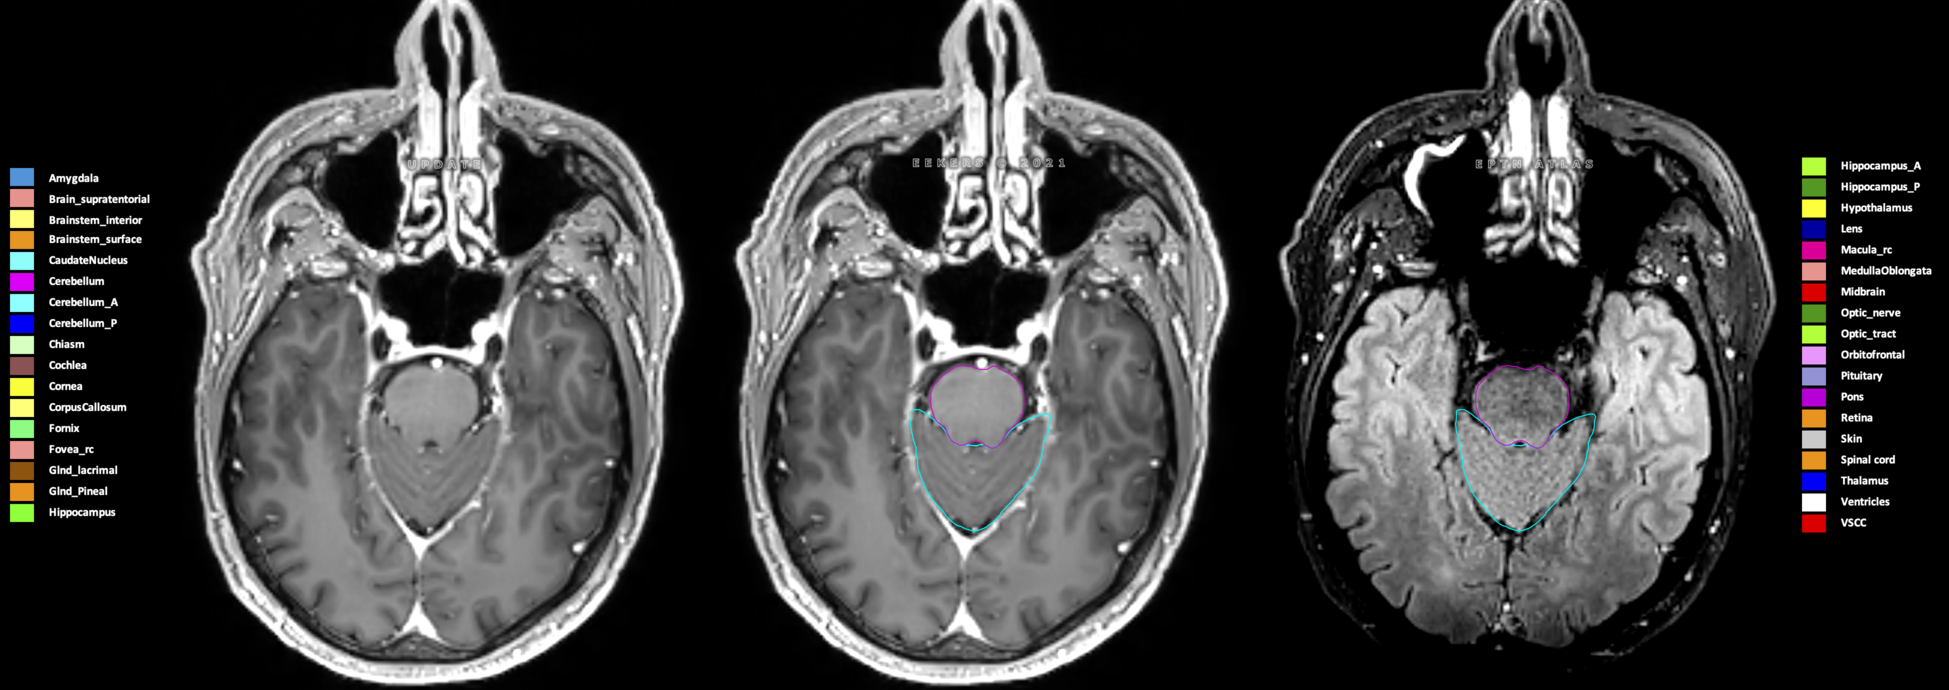

Eekers et al. have published an international neurological atlas for contouring of organs at risk in consensus with the European Particle Therapy Network (EPTN) in 2018 and an update in 2021. The purpose of this consensus atlas is to decrease inter- and intra-observer variability in delineating OARs relevant for neuro-oncology.

Included are all OARs known to be relevant for radiation-induced toxicity in neuro-oncology: brain, brainstem (midbrain, pons, medulla oblongata), chiasm, cerebellum (anterior & posterior), cochlea, cornea, hippocampus (anterior & posterior), hypothalamus, lens, lacrimal gland, optic nerve, pituitary, skin, and vestibular & semicircular canals. To further facilitate research on cognition, vision and radiological changes after irradiation of the brain, potential clinically-relevant OARs are included: amygdala, caudate nucleus, cerebellum (anterior & posterior), corpus callosum, fornix, macula, optic tract, orbitofrontal cortex, periventricular space (PVS), pineal gland, and thalamus.

Three-dimensional delineation of the 25 consensus OARs for neuro-oncology are shown on CT (WW/WL 120/40, 3000/600), 3T MR images, (T1Gd, T2FLAIR 1mm) and 7T MR (MP2RAGE 0.7 mm). All are presented in transversal, sagittal and coronal view.